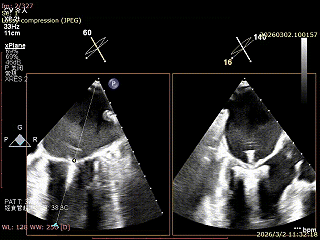

患者为房间隔缺损术后合并功能性二尖瓣反流(FMR),病变位于二尖瓣2区偏3区,因既往ASD修补史(可降解房间隔缺损封堵器),致房间隔穿刺区域存在瘢痕粘连、穿刺难度增加,于靠下靠后位置穿刺,避开房间隔缺损封堵伞,其余病变解剖结构相对简单;术前制定手术策略,拟使用1把XTR行二尖瓣修复,术中克服瘢痕粘连难点成功完成房间隔穿刺,穿刺点距二尖瓣瓣环平面3.1cm,将XTR‑CDS送入左心房,通过”A”旋钮旋转180度借高度,LVOT切面夹子严重Huge,使用”+”旋钮一键消除Huge,通过操控“M”旋钮将二尖瓣夹精准定位于2区正上方,完成弹道测试及Orientation调整后,于2区将夹子送入左心室,顺利捕捞并夹持瓣叶后缓慢闭合夹臂;TEE检查示二尖瓣反流充分降低至微量,二尖瓣双孔组织桥稳定,跨瓣压差2mmHg,肺静脉逆流明显改善,手术安全顺利结束。

XPLAN切面2区偏3区中重度反流